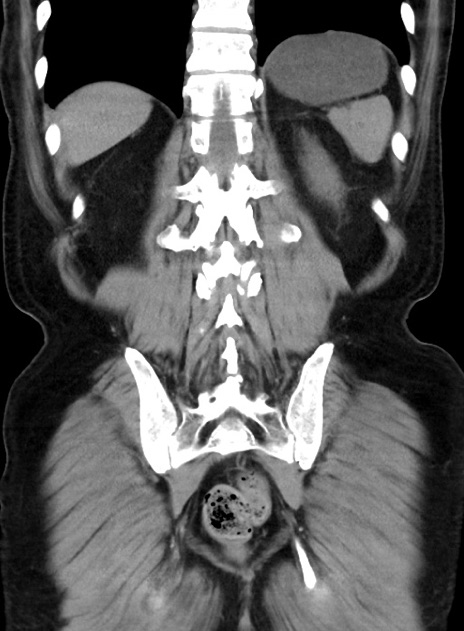

症例38(冠状断像)

【症例】70歳代 男性

【主訴】腹痛・嘔吐

【現病歴】昨晩より、嘔吐・腹痛あり。今朝になっても嘔吐あり。来院。

【既往歴】心臓バイパス手術、開腹胆摘、腸閉塞

【身体所見】BP 107/71mmHg、HR 116/min、腹部:平坦、軟、下腹部に軽度圧痛あり。反跳痛なし。

【データ】WBC 15100、CRP 0.32

横断像